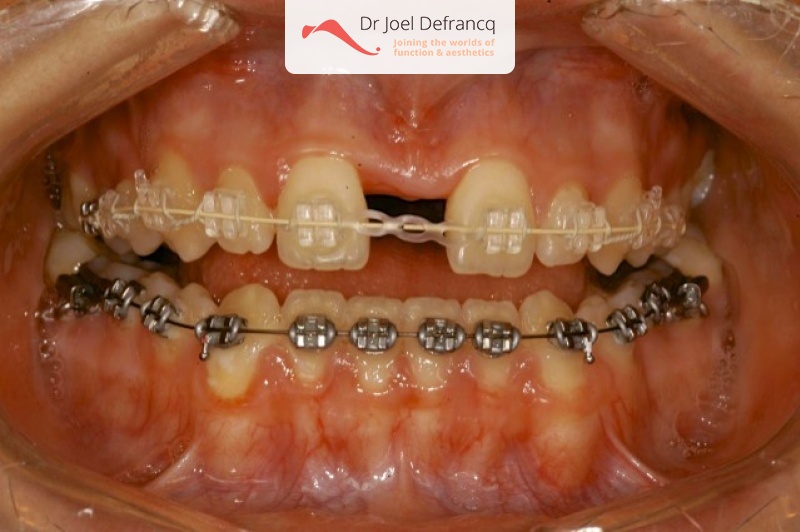

Kaakchirurgie

- Verlenging bovenkaak (Le Fort I)

- Kinchirurgie

- Verbreden bovenkaak (Smile distractor)